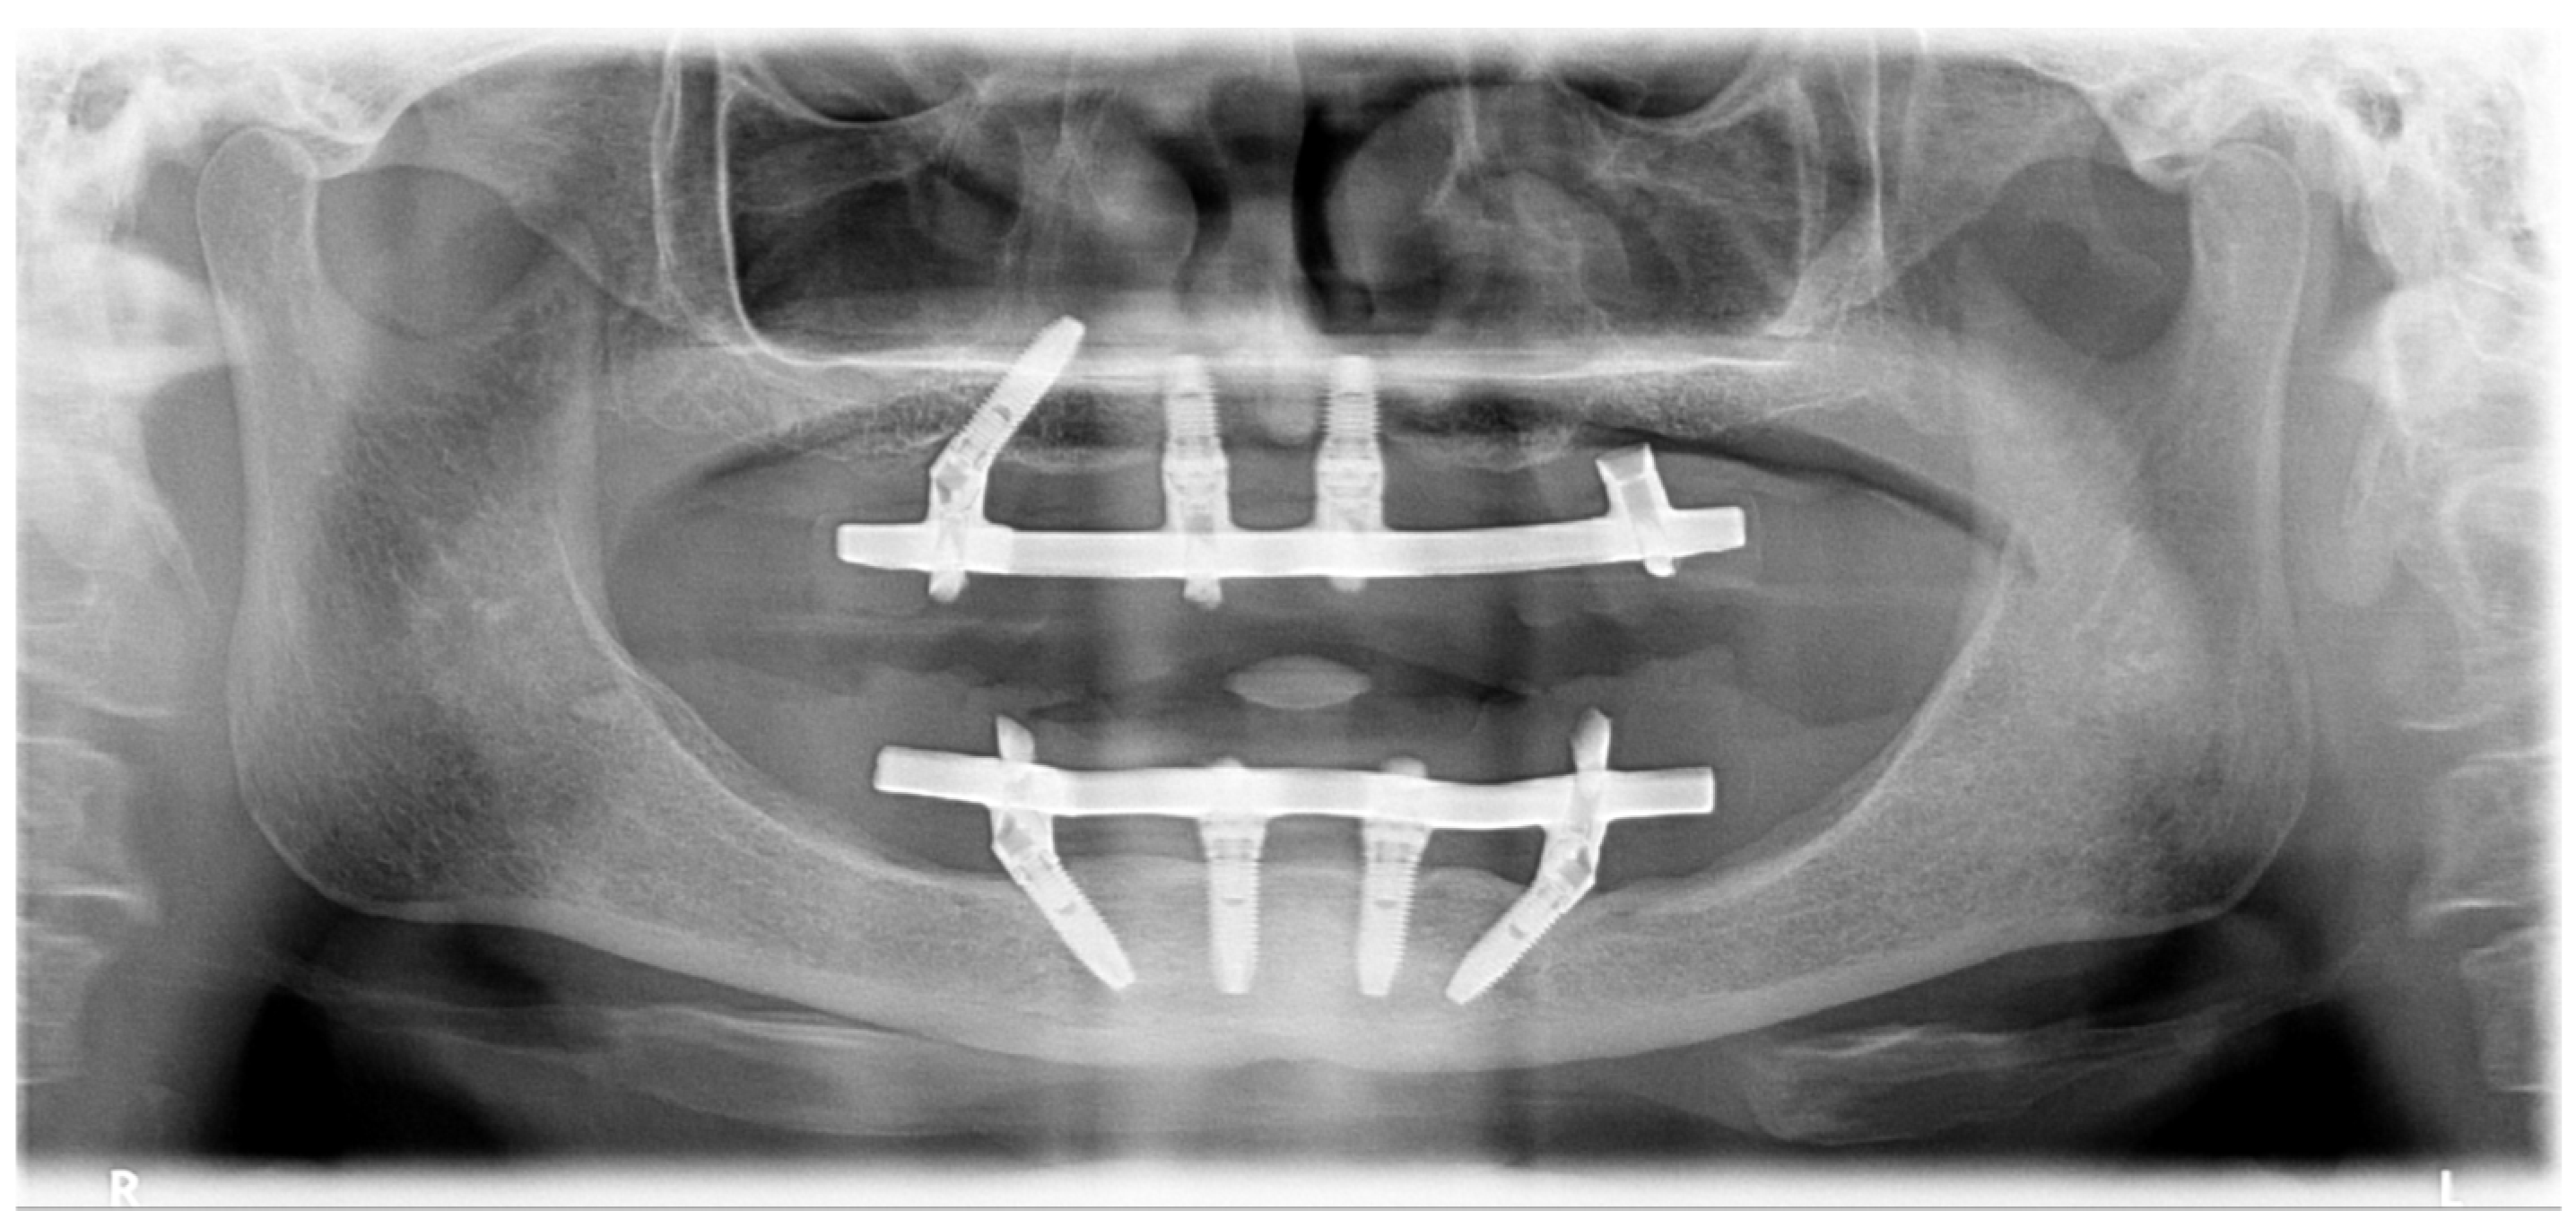

2.2. Patient 2